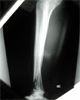

Result

Good return ankle motion